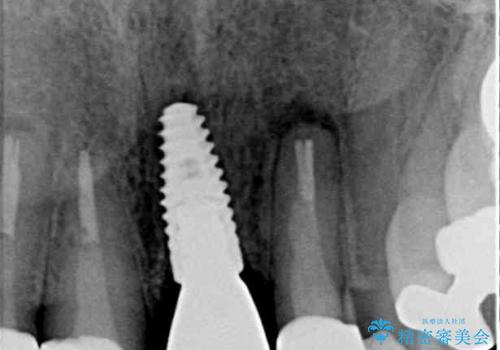

2. 折れてしまった前歯 インプラントによる補綴治療の治療中